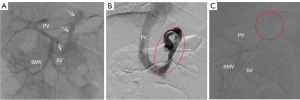

The 6-month postnatal follow-up revealed that the shunt vessel was still present, along with abnormal liver function tests showing increased alanine aminotransferase (ALT) and aspartate aminotransferase (AST) levels, as well as hypoproteinemia. The infant subsequently underwent percutaneous shunt treatment at another medical facility. An indirect venography performed through the SMV showed the abnormal shunt from the PV to the IVC (Figure 3A). A vascular occluder was deployed at the site of the shunt to successfully embolize the vessel (Figure 3B). Subsequent indirect venography performed through the SMV confirmed the absence of portal-to-IVC shunting (Figure 3C). The child’s postnatal prognosis at 1 year and 6 months was favorable.